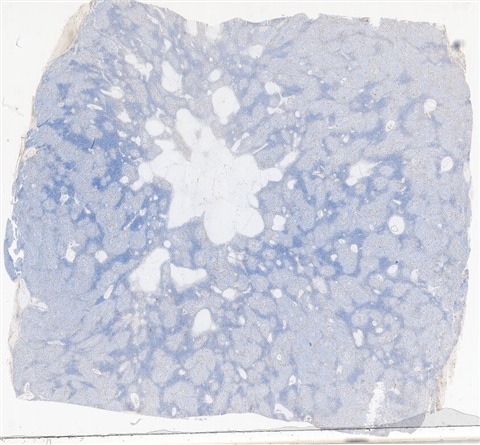

案例3 (6862)

性别:       年龄:65

患者详情: 患者3月余前在当地社区卫生服务中心体检发现血肌酐升高(109.8umo/L),无明显尿量减少,无颜面下肢浮肿无腰酸腰痛,无肉眼血尿,无关节疼痛,无皮疹红斑,开始未重枧及进一步诊治。10余天前患者到中山医院复查生化提示“肌酐200umol/L、尿素7.3mmol/L、尿酸637umol/L、白蛋白34g/L、球蛋白66g/L、蛋白电泳β15.0%、蛋白电泳Y42.6%”,同时其它检查提示“血lgG4 54.20g/L”。 CT:纵隔及双侧腋下多发肿大淋巴结,肺动脉干稍増粗,主动脉硬化,扫及双肾饱满,后腹膜发淋巴结。 PET-T:全身多区域淋巴结肿大、双侧泪腺、双侧颌下腺及胰腺体尾部饱满、双肾实质肿胀,左侧头皮局部增厚,伴FDG代谢增高,鼻咽顶后壁及前列腺腺体FDG代谢增高,上述病灶首先考虑IgG4相关性疾病所致可能,建议暖股沟淋巴结活检病理明确除外淋巴瘤。

大体所见: 结节一枚3*3*2cmA-C。

医院: 上海交通大学医学院附属仁济医院